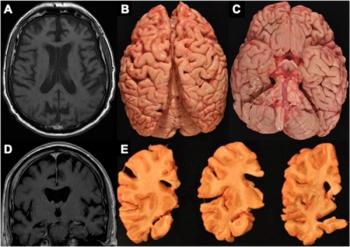

Emerging research suggests that frontotemporal atrophy on magnetic resonance imaging may be a key finding for chronic traumatic encephalopathy (CTE).